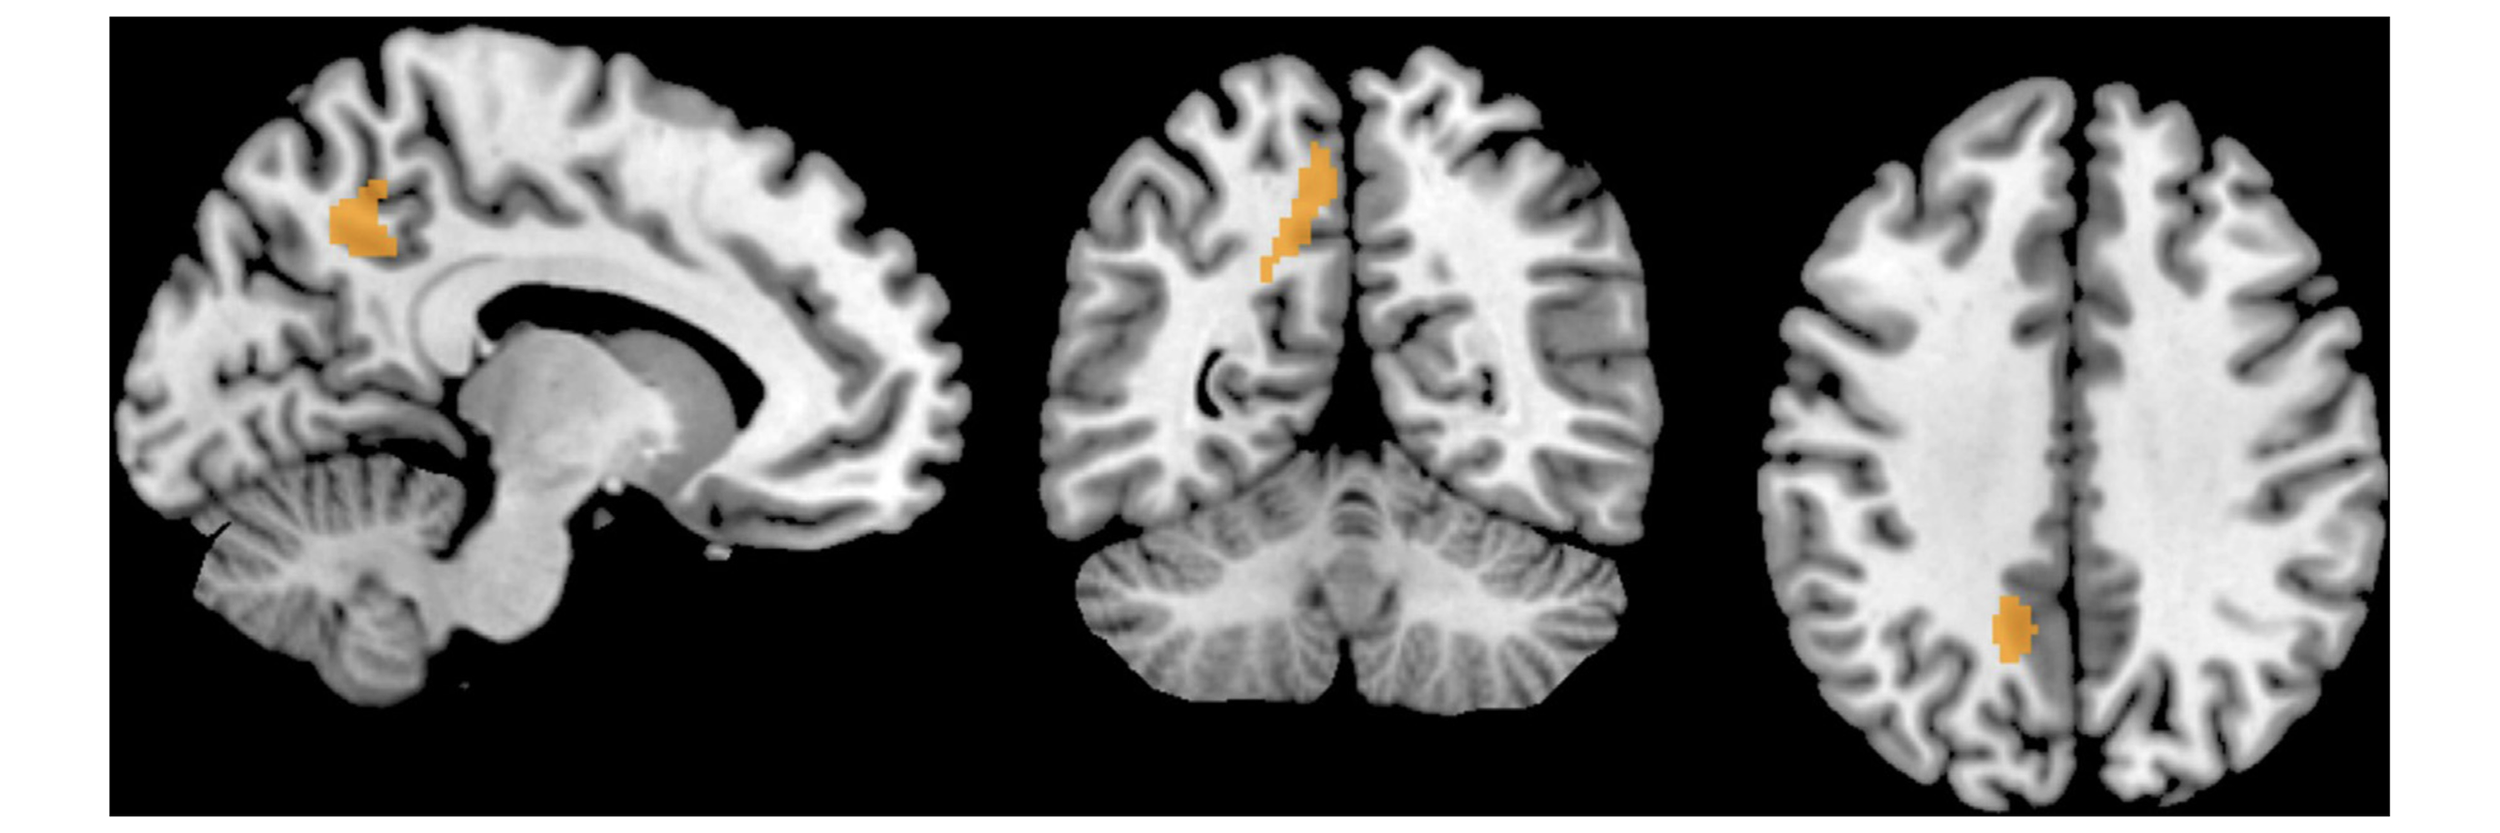

Fig. 2. Left Precuneus showing an increased functional connectivity in OCPD patients seen on sagittal (left), axial (in the middle) and coronal (right) views.

3.2 DMN differences between OCPD and Controls

Individuals with OCPD presented increased levels of functional connectivity in the left precuneus (MNI coordinates: x = -14, y= -52, z=40; Cluster size: 166 voxels; t=4.32, Z=3.56) when compared with heathy controls. The results were significant at a corrected for multiple comparisons p < 0.05 threshold determined by Monte Carlo simulation program (AlphaSim) (Fig. 2).